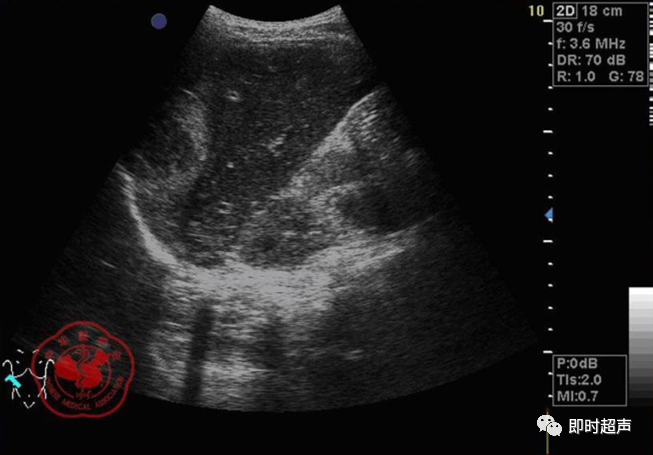

• GIST的发病机制与KIT信号通路的激活有关。• KIT是一种酪胺酸激酶跨膜受体蛋白,未经“装配”过的KIT蛋白是一种非活化的单体,参与细胞膜形成。几乎所有GIST都表达了KIT蛋白,而且大多突变的KIT基因保留了表达KIT蛋白的特性。c-kit内的突变主要见于恶性病例,特别是外显子11的点突变,还有外显子9、13和17,可以导致本质的或配体独立的c-kit激活,引发细胞的无序增殖和凋亡。这些具有功能的突变是GIST发病机理的关键,并且与肿瘤的恶性程度和预后较差相关。• GIST约75%发生于50岁以上老年人,中位年龄为58岁,无明显差异。• 可以发生在消化道从食道到肛门的任何部位,偶尔可原发于网膜、肠系膜和腹膜后,约50%发生在胃,25%发生在小肠,不足10%发生于食管、结肠及直肠。大体观察:肿块多境界清楚,类圆形,结节状,部分有假包膜。切面灰白、灰红,质韧,部分质嫩呈鱼肉状,伴有出血、坏死、囊性变。• 肿瘤组织主要由两种细胞组成,一种为长梭形细胞,细胞质丰富,嗜酸性,细胞核呈梭形或杆状;另一种为上皮样圆形或多角形细胞,细胞肥胖,胞质少。两种瘤细胞常呈束状、编织状或旋涡状排列。• 部分病例细胞异型明显,核分裂象增多,可见病理性核分裂象和瘤巨细胞。梭形细胞界不清楚,胞质丰富,淡染,轻度嗜伊红或略嗜碱,可有纤细、长梭形、短梭形或胖梭形、卵圆形,可见核仁。细胞核两端钝圆,部分病例胞质呈空泡状,位于核一端形成核端空泡胞,多呈交叉束状、旋涡状、席纹状及栅栏状排列。上皮样细胞胞浆丰富或透亮,多呈弥漫片状、束状或巢状排列。肿瘤间质可有出血、囊性变、坏死及黏液变,可见炎性细胞浸润。CD34抗原是一种115kd的糖基化蛋白,50%~80% GIST的CD34表达为阳性,CD34对鉴别GIST和典型的平滑肌瘤,神经鞘瘤还是非常有用的标记物,因后两者的CD34一般是阴性的。但CD34在诊断GIST上其特异性受到限制,一般情况下CD34多与CD117联合应用,方能提高GIST的诊断率。• 与肿瘤大小、发生部位、肿物与肠壁的关系以及肿瘤的良恶性有关。• 肿瘤较小者(直径小于2cm)常无症状,往往在体检和其它手术时无意中发现。• 肿瘤发生于胃肠道腔内时大多表现为呕吐、腹痛及消化道出血,而发生于胃肠道腔外的则主要表现为腹部包块。• 最常见的临床症状是中上腹部不适、腹部肿块及便血。• 对于临床发现的消化道(包括肠系膜、网膜、后腹膜)实体肿瘤,在排除其他常见肿瘤后,才考虑GIST。目前,诊断GIST有三条标准:③肿瘤组织具有梭形细胞和上皮样细胞两种基本细胞成分的病理学特征。这是诊断GIST金标准。CD117阳性者或CD117阴性而CD34阳性者,且伴平滑肌和神经双向分化或无分化者,可诊断为GISTs;以Desmin和SMA强阳性,而CD117阴性诊断为平滑肌肿瘤;以S-100阳性,CD117、Desmin、SMA均阴性诊断为神经鞘瘤。• GISTs的分型与组织学良恶性的关系:研究证实GISTs非单一分化的肿瘤,具有多向分化。• 当前GISTs的良性、交界性和恶性判断标准多参照Amin等提出的标准:②交界性:核分裂<5/50HPF,但肿瘤>5cm;• 另外研究显示,平滑肌型大多数为良性,少数为交界性和恶性,神经源型为恶性,双向分化亚型和未分化型为交界性和恶性,提示GISTs的分化型与其良恶性之间有一定关系。• 胃间质瘤早期多局部侵犯,后期出现肝转移和腹腔内种植,小肠间质瘤早期即可出现转移• 主要有超声扫描(检出率30%左右)、纤维内镜、超声内镜、CT、MRI、普通X• 线检查(胃肠钡餐造影、小肠插管气钡双重造影)、选择性血管造影检查等。• 不同部位的GIST,各种检查方法的敏感性不同。以CT检查为佳,尤其是螺旋CT,分辨率最高,可以三维重建,直接显示肿瘤大小、形态、密度、内部结构、边界,对邻近组织的侵犯也看得很清楚,同时还可观察其他部位的转移灶,有利于分期、鉴别与诊断。• MRI具有多轴成像及反映肿瘤内部成分的优点,尤其是动态扫描及各种新的扫描系列的出现更使其可以普及应用。• DSA检查对于GIST,特别是有消化道出血的患者更有价值。• 上述影像学检查表现并非特异性,与胃肠道平滑肌肿瘤、神经源性肿瘤鉴别困难。明确诊断要依赖病理免疫组化等手段。• 超声图像特征 肿物体积较小者(直径< 5. 0 cm )多为实性病变, 呈类圆形, 边界清晰, 内部回声多为较均匀的低回声。• 肿物体积较大者(直径> 5. 0 cm ) 多为混合性病变,呈不规则圆形或分叶状, 多数边界尚清晰, 以实性为主的病变内部为不均质中低回声伴不规则液性区及斑点状强回声; 以囊性为主的病变囊壁较厚,有分隔, 部分囊腔内可见点状、团状低回声。CDFI显示肿物实质回声内血流均较丰富。病例1:患者男, 62岁。自扪腹部包块2月余,包块增大20天就诊。查体:腹部平坦,无腹壁静脉曲张,无胃肠型及蠕动波,腹肌软,剑突下5cm处及左肋缘下可触及一质韧包块,大小约15*12cm,活动度差,边界尚清,包块深压痛,全腹无反跳痛。化验检查AFP:3.66(1.09-8.04)ng/ml,CEA:2.85(0-5)ng/ml。体格检查:一般情况良好,全腹软、平坦,腹部无压痛。超声检查:患者仰卧位时左上腹于胰尾前方可见一大小约6. 1 cm ×5. 8 cm ×5. 3 cm实性均质低回声,形态规则,包膜完整,边界清晰,活动度大;右侧卧时,肿块移至胰头右前方(图1) ;于其内探及丰富血流信号。体格检查:一般情况良好,腹丰满,上腹部有轻压痛,未扪及明显肿块。超声检查:患者仰卧位时左上腹于胰尾前方、脾门处可见一大小约10. 0 cm×8. 8 cm×7. 6 cm 实性低回声(图2) ,形态规则,包膜完整,边界清晰,肿块活动度大;右侧卧时,肿块移至左肝下间隙,回声尚均质;于其内探及较丰富血流信号(图3) 。图3 腹腔低回声肿块位于左肝下间隙,于低回声肿块内探及较丰富血流信号向壁外生长的胃肠道间质瘤, st为胃腔,箭头所指为胃壁, T为向外生的肿瘤• 胃间质瘤的定位准确率要高于十二指肠及小肠间质瘤,这主要是因为胃的解剖位置相对固定,且通过饮水使胃腔充盈,可清晰的显示胃壁的各层结构及肿块与胃壁的关系。肿块多表现为粘膜下、肌层或浆膜下低至中等回声团块,可向腔内、腔外或腔内外生长。但当肿瘤较大或浸润周围脏器时,超声定位仍有困难, 因此,超声如发现上腹部肿块且怀疑来源于胃者,应尽可能嘱其饮水充盈胃腔,并多角度、多切面观察肿块与周围脏器的关系,以提高定位的准确性。• 十二指肠间质瘤的定位亦较准确,但降部的外生性肿块常与胰头粘连而误诊为胰腺肿瘤回声均匀且位置较深的间质瘤亦可能误为胰头周围淋巴结。• 空、回肠间质瘤常因肿块较大,多发,位置不固定而难以定位,往往误诊为腹、盆腔或腹膜后肿瘤,超声检查如发现肿块局部肠壁增厚,肿块与肠道随呼吸同步运动时可作出定位诊断。• GIST的声像图表现有助于其良、恶性的鉴别:良性肿瘤多体积较小,圆形或椭圆形,回声均匀,边界清晰。恶性肿瘤多较大,呈不规则分叶状,回声不均匀,内部易出血、坏死、囊变。• 肿瘤长径与肿瘤内部是否出现无回声区在良、恶性病变之间的差异有统计学意义,是判断良恶性的有效征象。• 如以肿瘤长径>5cm为诊断恶性标准,其敏感性、特异性及准确性均较理想。超声可为临床提供胃肠道间质瘤的部位、大小、边界、回声等较多有用信息,一部分病例可作出定位、定性诊断,并可在术后或复发患者药物治疗期间对其进行动态观察;CDFI方便快捷、无需造影剂即可对间质瘤周边及内部血流进行观察,可为临床医师提供肿瘤血供情况。但未发现腹腔或肝脏转移时,超声判断胃肠道间质瘤性质有一定难度。• 目前临床上对GISTs的治疗效果并不十分满意。治疗仍以手术为主,对无法手术切除或已有转移的GISTs患者进行甲磺酸伊马替尼化疗。• 手术方式取决于肿瘤大小、部位和术中冰冻切片结果等。• 发生在胃的间质瘤,可首选胃大部切除术;发生在十二指肠的间质瘤可行保留胰头的十二指肠切除术或胰十二指肠切除术;发生在小肠的间质瘤可行肿瘤肠段切除术;发生于结肠的间质瘤可行左半或右半结肠切除术;发生于直肠的间质瘤可行肿瘤局部切除术。一般情况下无需淋巴结清扫。• 术后随访监测,复发者单个病灶可考虑手术切除;多发或转移特征者应试行甲磺酸伊马替尼化疗,并监测肿瘤大小及数目的改变。• 随着分子靶点药物进入肿瘤临床,一种小分子化合物———酪胺酸激酶受体抑制剂,美国称为Gleevec,欧洲叫做Glivec(格列卫),在治疗GIST和慢性粒细胞白血病方面有其独特的作用。已知细胞膜表面上皮生长因子受体酪胺酸激酶抑制剂大致分为两大类:一类是小分子化合物;另一类是特异性抗体。利用抑制酪胺酸激酶的活性,对处于增殖期状态的病变具有治疗的作用。Glivec在体外、体内和细胞水平都可强烈抑制酪胺酸激酶的活性,是干细胞因子(SDCF)受体KIT的强抑制剂。• Glivec推荐用量为400mg(4片),每日一次, 3个月为一疗程。如服3个月后无效可加至600mg/d~800mg/d(6~8片)[18];若仍无效果不再增量应停止治疗。• Glivec治疗进展转移的GIST总有效率为50%左右,比传统化疗有效率高十倍以上;肿瘤生长控制率达80%以上,起效最快在服药后24h之内,使症状改善如疼痛缓解;平均起效时间为13周(约3个月)。患者体力状况改善是又一突出效果。2/3患者治疗后无症状可如健康人生活工作。• Brainard等研究发现间质瘤预后差的前两位因素为肿瘤大小和核分裂象,故对于间质瘤直径>5cm和核分裂象>5/50HPF的患者应给予口服Glivec。最近,Liu报道口服Glivec治疗可使85%患者的病情得到控制。